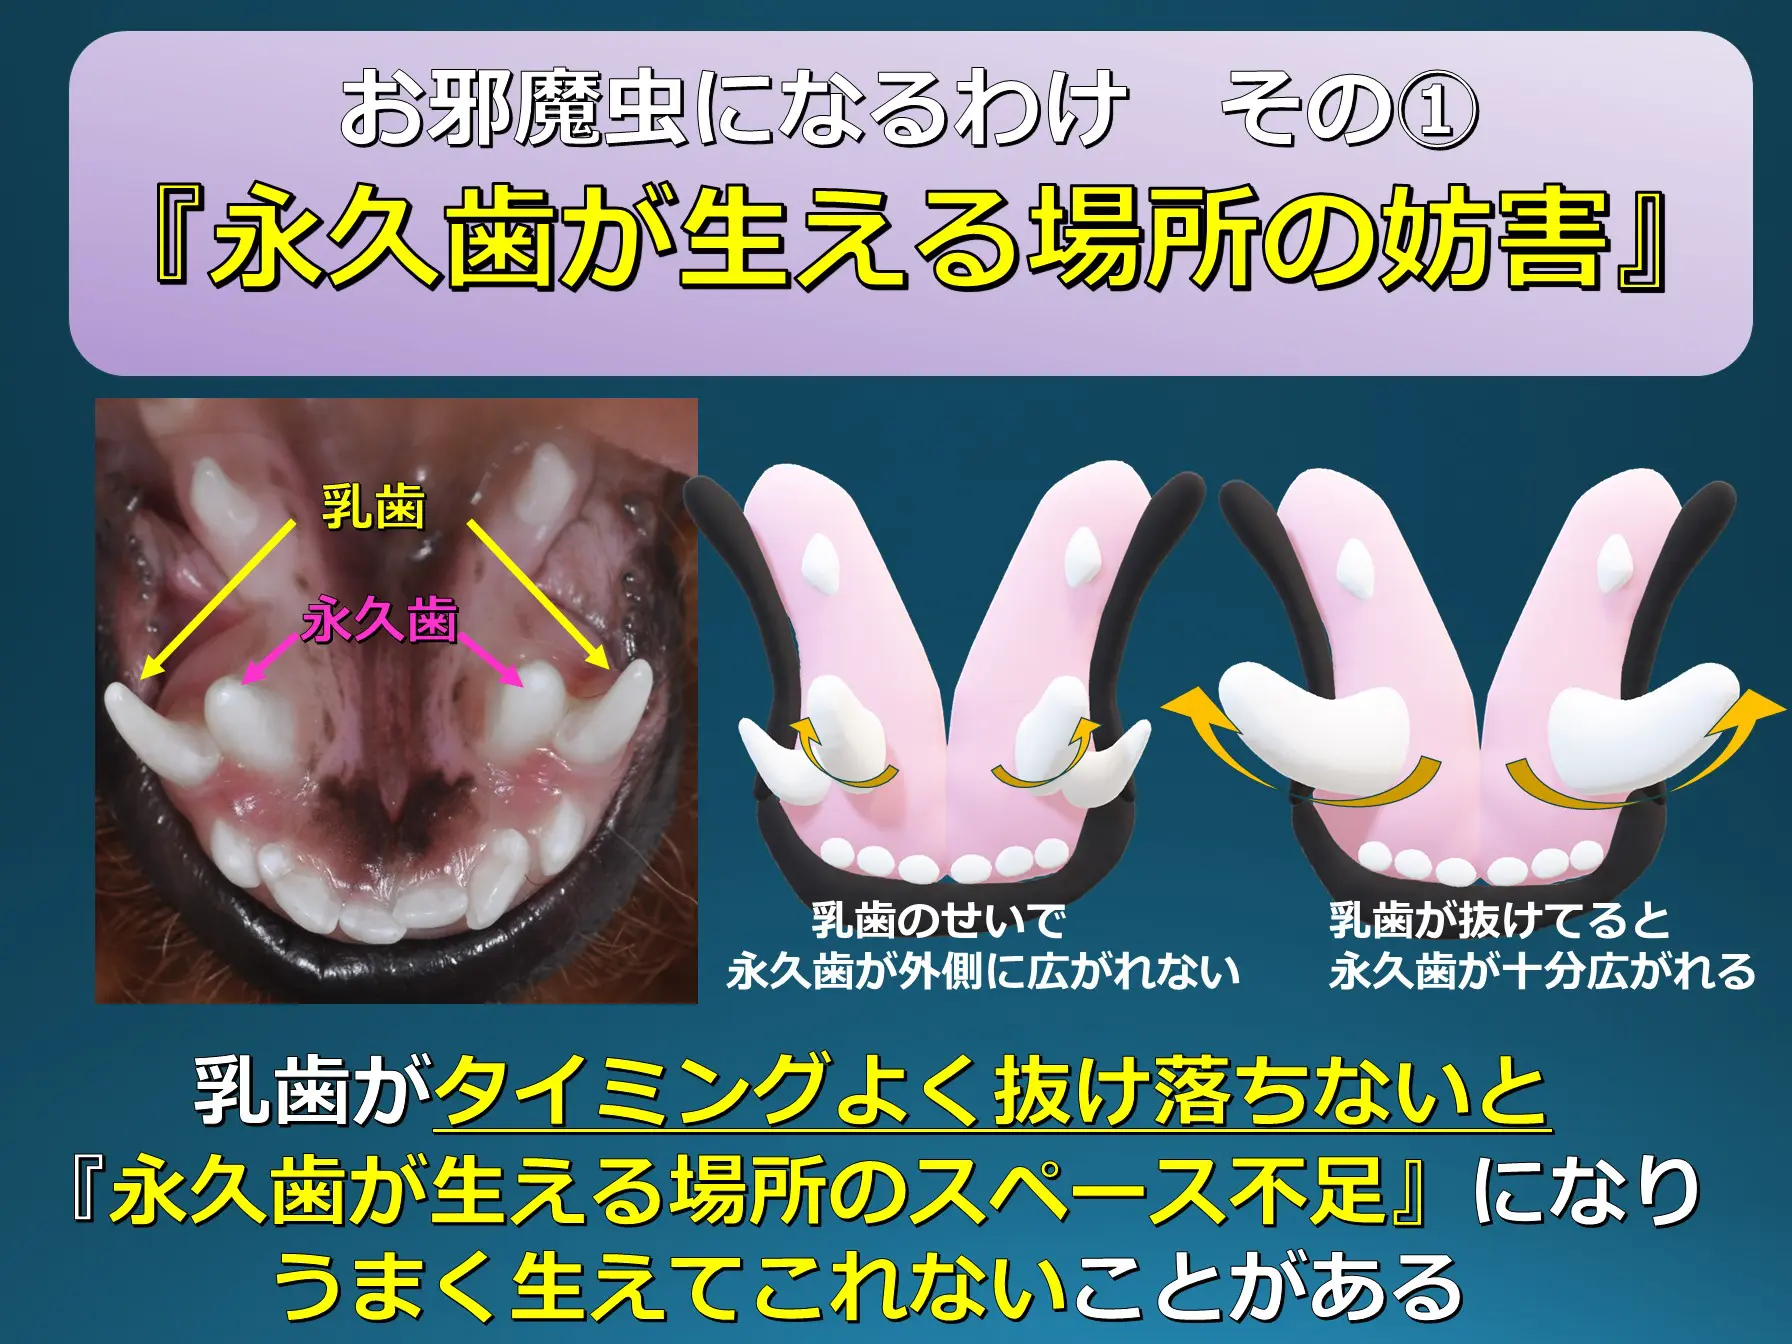

乳歯がグラグラ!なかなか抜けない 乳歯が抜けていないのに永久歯が生えてきた時の対処法大阪・岸和田のくすべ歯科。

獣医師が解説 犬の乳歯遺残とは?原因や健康へのリスク、対処法について三鷹市のかえで動物病院三鷹・武蔵境のかえで動物病院土日も診療24時間Web予約。

抜けぬ乳歯はお邪魔虫 – 犬猫医療センター笠松動物病院。

乳歯が抜けない!歯がなんか多い気がする。犬や猫の乳歯遺残について解説します。